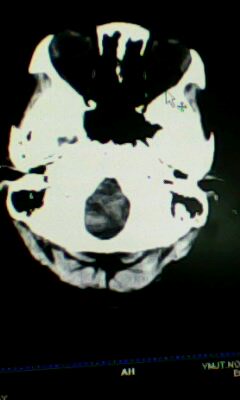

标题: CT25338:女 14岁 3岁时检查为脑积水 现在发育滞后 偶有尿失 [打印本页]

标题: CT25338:女 14岁 3岁时检查为脑积水 现在发育滞后 偶有尿失

蛛网膜囊肿!

左侧颞枕叶区密度异常?